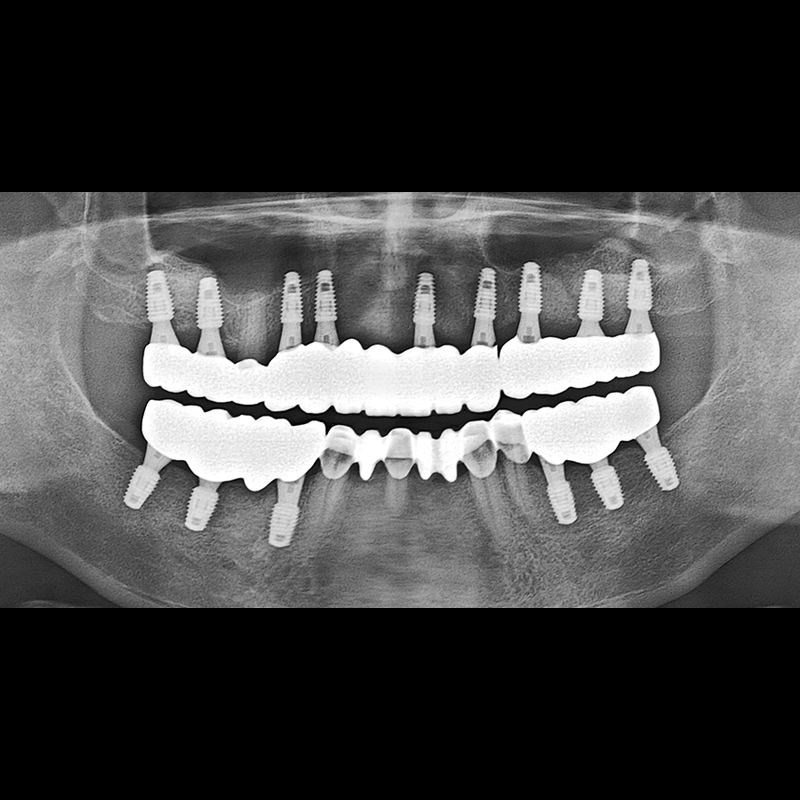

IMPLANT

BEFORE AFTER